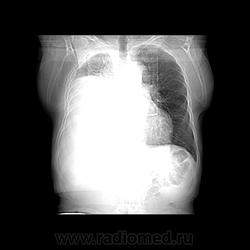

Пожилой мужчина, лечился по н/д правостороннней пневмонии в терап/отделении. Жалобы на одышку, кашель. По результатам Р-контроля после лечения направлен на КТ легких с диагнозом: плеврит справа, распад? В корне правого легкого вижу объёмное образование, с распадом. Смущают размеры плеврита,очень много жидкости, почти до 3 ребра. Анализы крови спокойные- L4,0-6,6, СОЭ 12-16мм. Неужто ТБС, отсев бы был при таком огромном поражении. В посеве мокроты-100% высев клебсиэллы пневмоние. Мокрота на общий анализ в работе-собирает с трудом, изза отсутствия мокроты. Плевральную пункцию еще не проводили. Н азначила бронхоскопию и плеврал пункцию. Как думаете, уважаемые коллеги, это онкопроцесс или тбс распад?

Не смотря дайкомы, только по рентгенограмме, предположил бы центральный рак правого легкого. Потому что большой гидроторакс, без смещения средостения в здоровую сторону, как правило, соответствует раковому ателектазу.

По-моему там и слева лимфаденопатия корня легкого, гидроторакс туберкулезной этиологии редко у пожилых бывает

Коллеги, распада там нет, это вас медиастинальное окно подвело. В грудине тоже все в порядке. Да и компрессия позвонка "старая".

Рак.

Небольшое количество увеличенных лимфоузлов, и те - не сказать, чтоб были очень крупными. От эмпиемы до онкологии... Умеренное количество жидкости в перикарде, толщиной слоя до 13-14 мм. При подобной картине не вижу смысла гадать по сжатому лёгкому, пишу так: массивный выпот справа, около 2500 мл, диафрагма оттеснена жидкостью каудально, печень (!!!) смещена каудально и вправо. Легкое справа значительно компрессировано жидкостью, оценка проходимости бронхов и состояния легочной паренхимы (кроме имеющейся эмфиземы) практически невозможна. Необходима пункция плевральной полости справа (цитология, ВК, посев на микрофлору и проч), КТ-контроль после эвакуации жидкости.